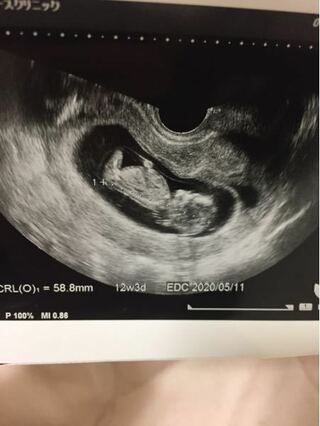

12週3日のエコー写真の見方について教えてください 初めての妊娠 Yahoo 知恵袋